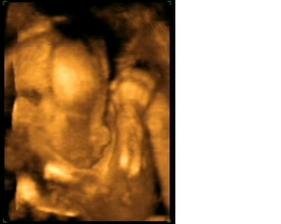

Termín pôrodu vychádza na 24.12.2009 - takže bude vianočný darček 🙂)) 6.7.odber krvi na AFP testy, 15.7.su vysledky a vsetko je ok 🙂) 14.8. 4D ultrazvuk - máme 413g (22tt) a vyzerá to na dievčatko 🙂)) TP podla velkosti: 23.12. 13.10. - utz v 30tt, resp.takmer v 31tt..máme 1700g..podľa veľkosti 31+2tt a všetko ok 🙂)